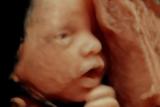

Հղիությունը շաբաթներով՝ ըստ ամիսների

Ապագա մոր շաբաթը-շաբաթի մեծացող որովայնը հղիության ինքնատիպ խորհրդանշանն է: Որովայնը չափերով մեծանում է պտղի, արգանդի աճի և շուրջպտղային հեղուկի (ապագա երեխայի կենսամիջավայրը) հաշվին: Որովայնի մաշկի խնամքով պետք է զբաղվել...